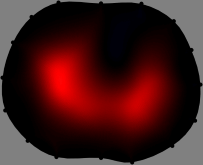

for [23]. This shows that the column vector is like an EEG (electroencephalography) data induced by dipole sources with directions at locations . Given that two dipole sources at distant locations produce mutually independent data, the correlation between and decreases with the distance between and . Fig. 2 shows a few images of the correlation as a function of for four different positions . The correlation decreases rapidly as the distance increases. In the green regions where the correlation is almost zero, is nearly orthogonal to .

Fig. 2 shows that if and are far from each other, the corresponding columns of the sensitivity matrix are nearly orthogonal. This somewhat orthogonal structure of the sensitivity matrix motivates an algebraic formula that directly computes the local ensemble average of conductivity changes at each point using the inner product between changes in the data and a scaled sensitivity vector at that point: